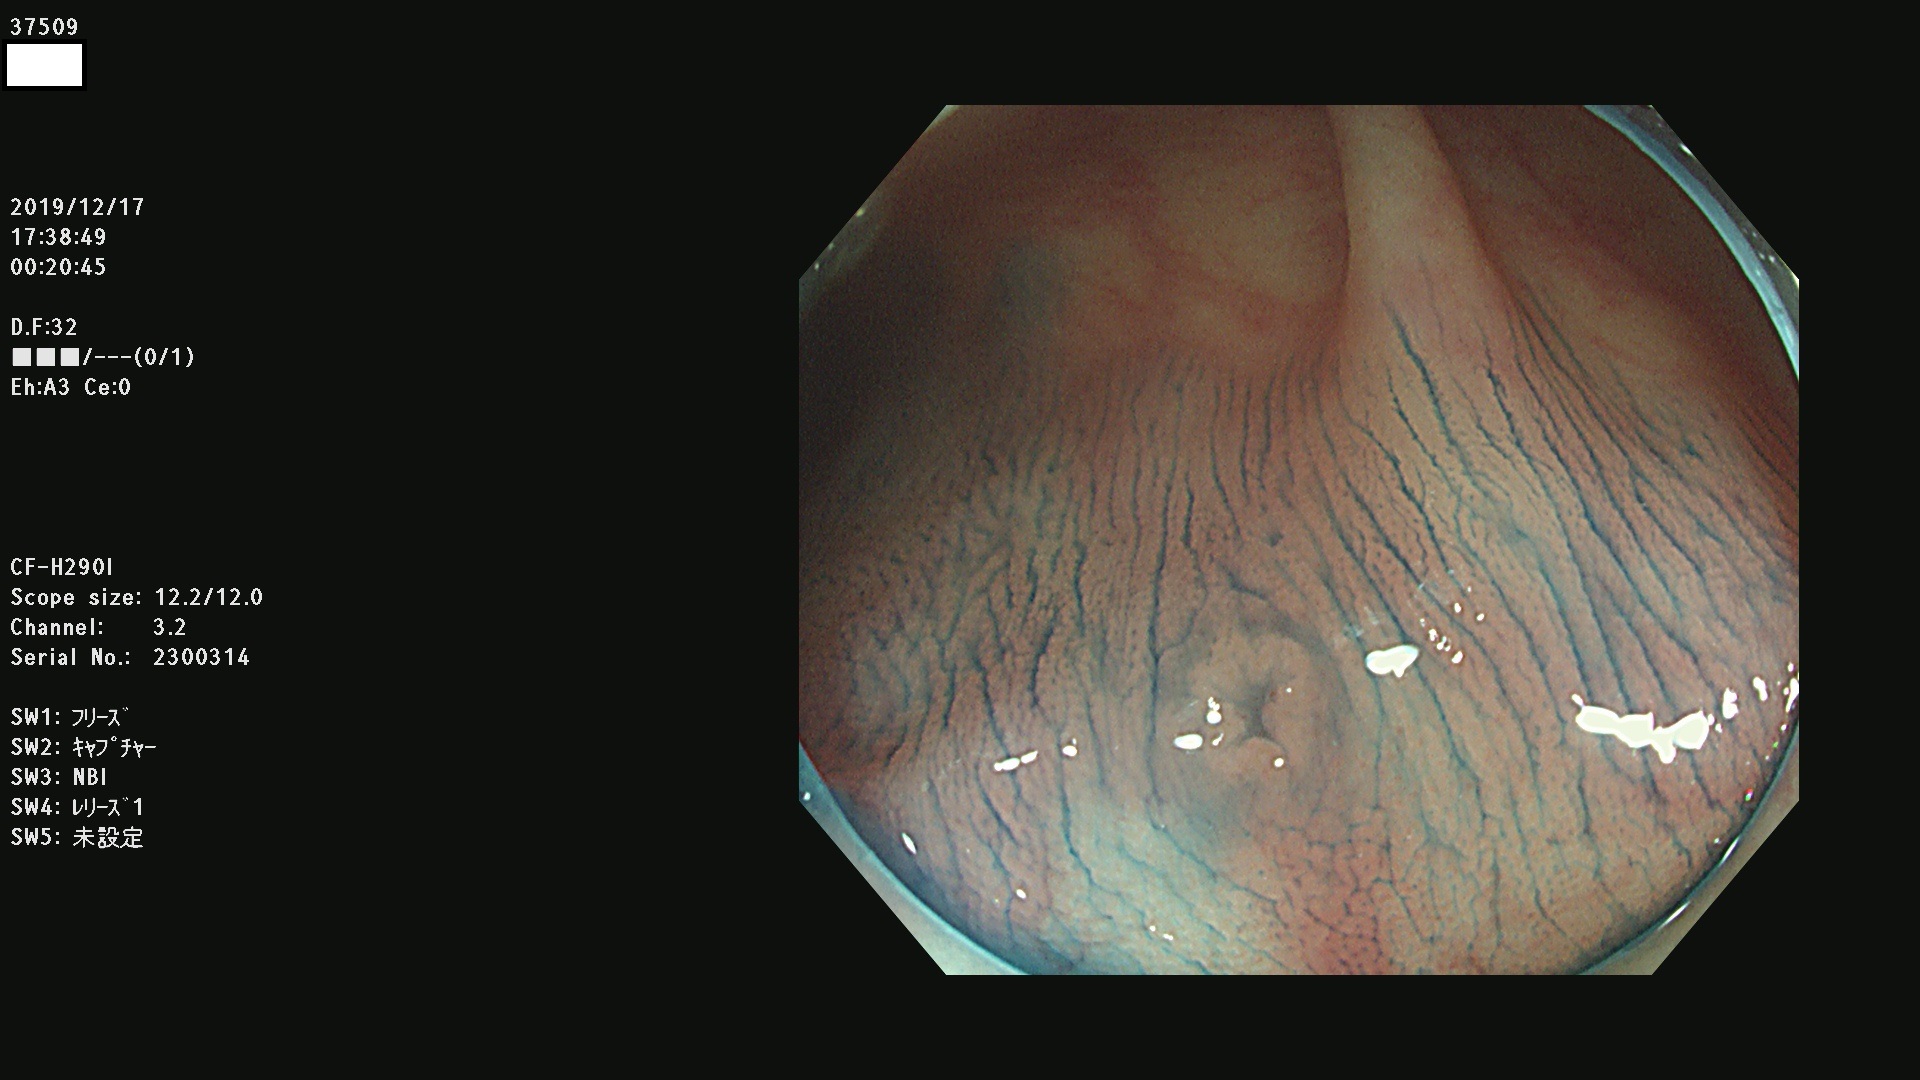

腺腫発見率 67 % (カルテ番号 37500〜37599の100名の方の検査結果で集計)大腸癌検診最新情報

以下のカルテ番号の方に腺腫(Adenoma,Group3〜5)が見つかりました(集計法)

37500 37502 37503 37505 37508 37509 37510 37511 37512 37513 37514 37517 37519 37520 37521 37525 37526(SSAPのみ) 37527 37528 37529 37531 37532 37533 37534 37536 37538(SSAPのみ) 37539 37541 37542 37543 37547 37548 37549(SSAPのみ) 37550 37552 37555 37556 37561 37562 37563(SSAPのみ) 37564 37565 37566 37567 37568 37570 37571 37572 37573 37574 37575(SSAPのみ) 37576 37577 37579 37580 37582 37583 37586(SSAPのみ) 37587 37588(SSAPのみ) 37590 37593(SSAPのみ) 37594 37596 37597(SSAPのみ) 37598 37599

発見困難で危険性の高い平坦型病変(上記100名より抽出) ![]()